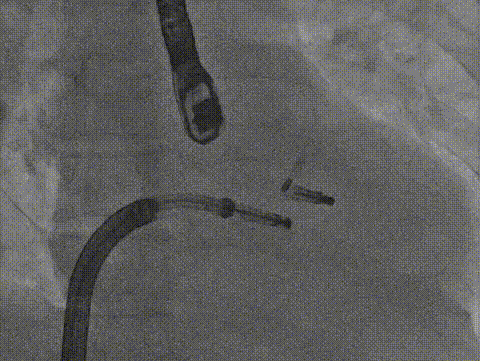

术中影像

房间隔穿刺

导引鞘置入左房

长宽夹打弯至瓣上

调整Orientation